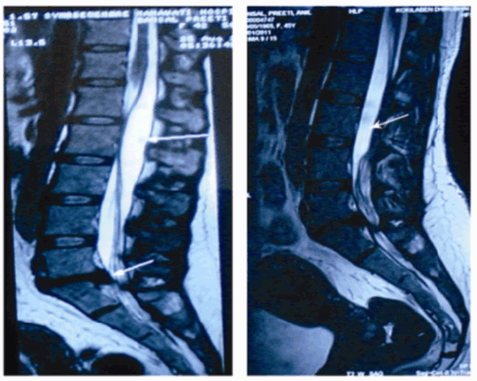

The patient was advised surgery for the removal of cyst with L5-S1 microdiscectomy, but the patient refused surgery and continued her activities, managing well with oral analgesics intermittently for a period of 12 to 14 months. However, later she presented with acute aggravation of lumbar axial pain and spasms with poor response to analgesics. The pain was continuous, radiating to both lower limbs, not relieved by rest, along with perineal pain and hypoesthesia. Motor power was normal in both lower limbs with urinary urgency and frequency without difficulty in initiation and incontinence. Repeat MRI showed no interval change in the degree of disc extrusion, however the cyst that was initially on the posterior aspect of the filum and cauda equina, had shifted anteriorly with posterior displacement of cauda (Figure 3).

Figure 3: Showing change in position of the cyst from the posterior aspect of the filum and cauda equina to anterior aspect over a period of 12 months.